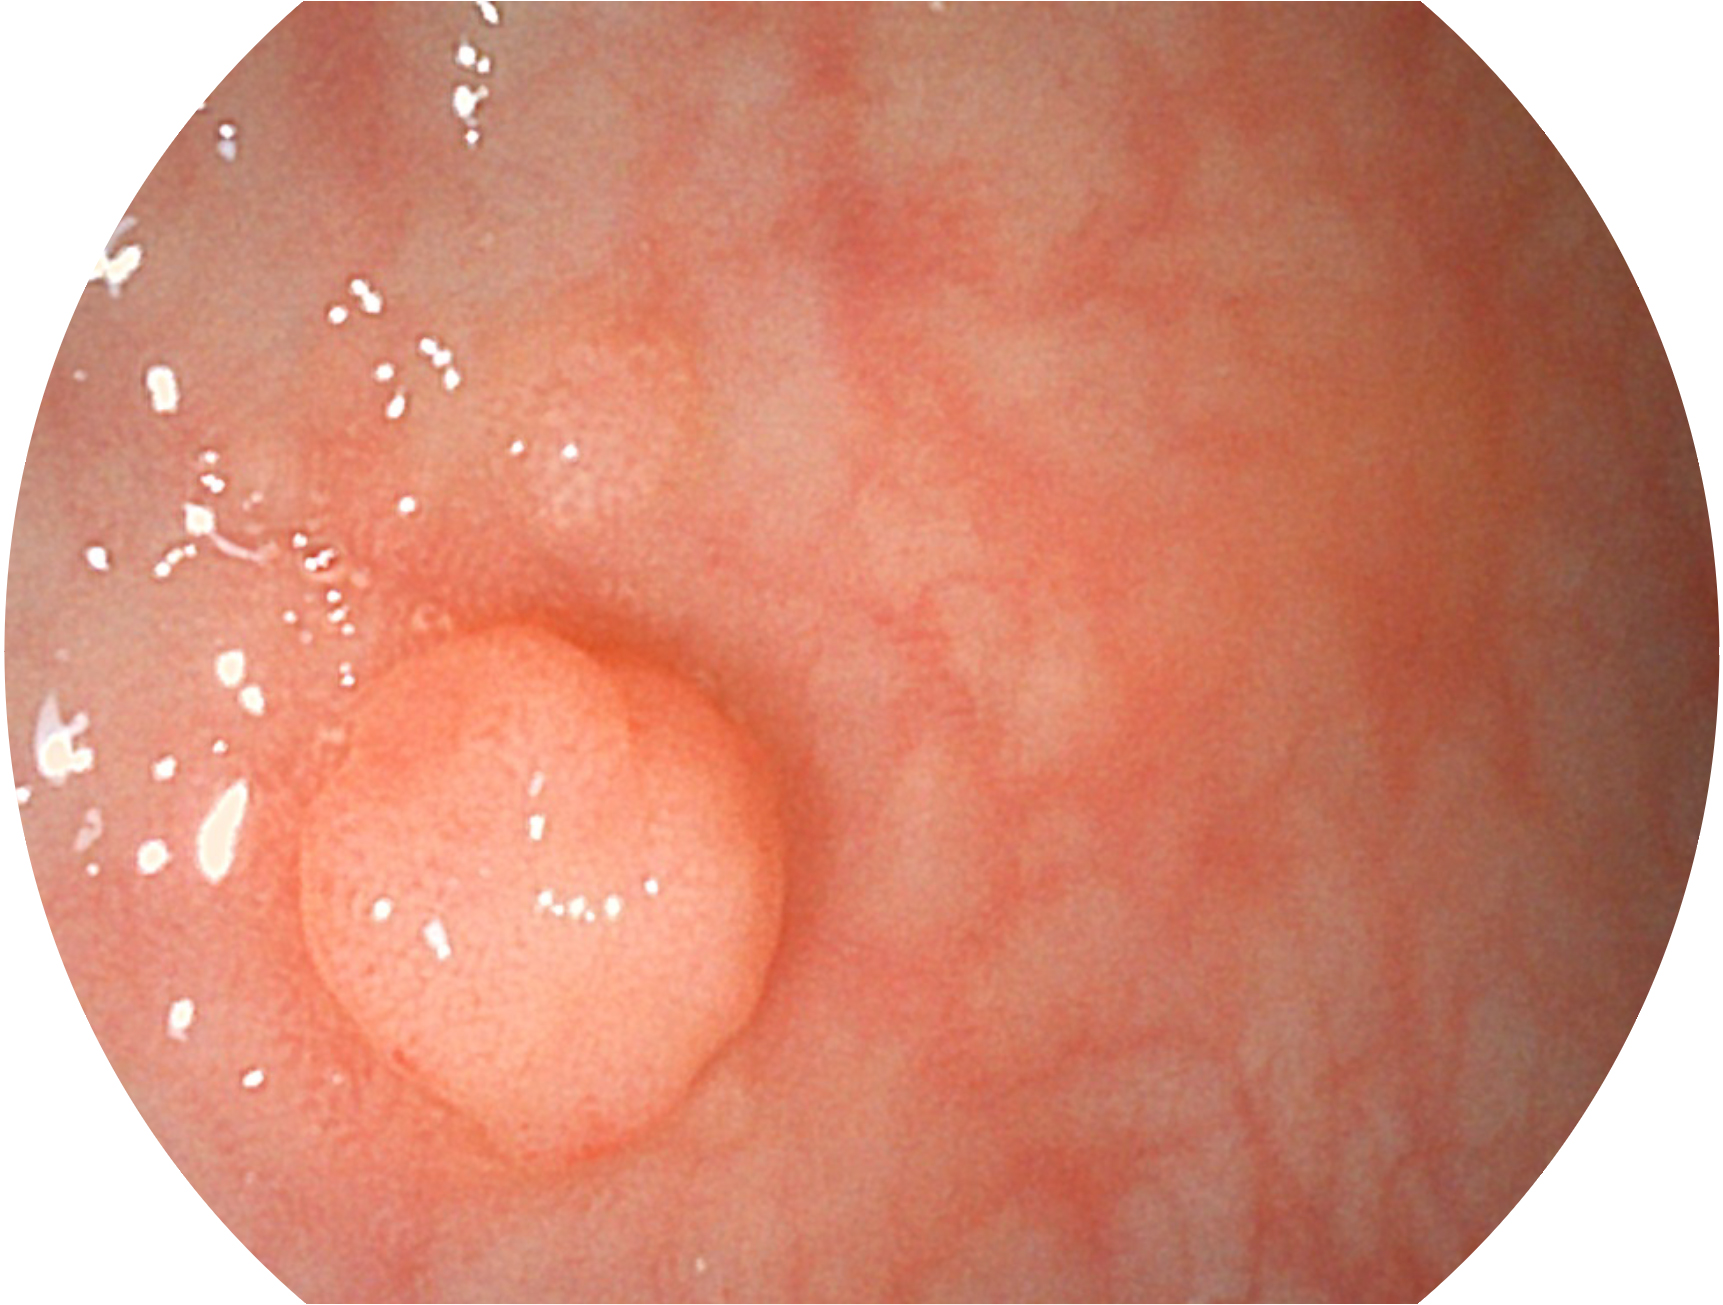

1xBET新开发的内镜染色技术,主要是基于多波长LED 光源的开发,VLS-55Q 四波长LED 光源是由四个不同颜色的LED光按照相应照明模式所规定的特定发光比例进行合束后形成,合束后形成的照明光的光谱由红光、绿光、蓝光及蓝紫光这四个不同的波段范围构成。具有更高光谱自由度,通过光谱比例的控制,实现了聚谱成像技术,英文全称为“Spectral Focused Imaging, SFI”,缩写为“SFI”和光电复合染色成像技术,英文全称为“Versatile Intelligent Staining Technology, VIST”,缩写为“VIST”。